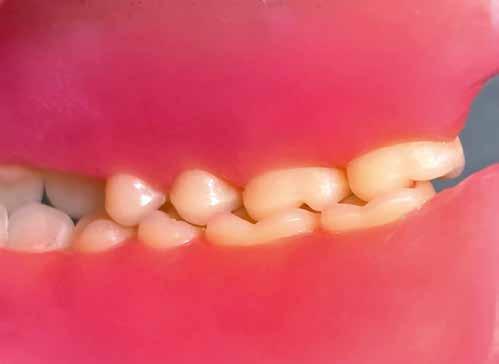

A CAD/CAM elterjedése ellenére az analóg eljárások nem szűntek meg funkcionálni. Esetbemutatásunk demonstrálja, hogyan rehabilitáltunk sikeresen az esztétikus zónában jól bevált munkamenettel, de új préskerámia recepttel. Az eredmény: természetes transzlucencia, opaleszcencia, fluoreszcencia – és egy boldog páciens.

A kiindulási helyzet recessziókkal és szabálytalan éli lefutással.

A pácienseset

Ötvenéves hölgy elégedetlen volt felső frontfogai esztétikai megjelenésével. Ezért elment a rendelőbe. Klinikailag vesztibulárisan két nagy kompozittömés volt megfigyelhető, széli elszíneződéssel. Az élek lefutása egyenetlen, aszimmetrikus volt. A frontfogakon recessziók és a nyakak szabaddá válása volt megfigyelhető. A hölgy a fogív gyors restauratív nivellálását kívánta. A nagymetszők közötti diasztémát csökkenteni kellett, de nem zárni, hogy megmaradhasson az optimális hossz-szélesség arány. A recessziók kötőszöveti fedését műtéttel kizárta. Viaszmintázat és intraorális mock-up segítségével szimuláltuk a teljes kerámiahéjakat, illetve segítettük a minimálinvazív preparációt a zománc területén. A páciens világos színű restaurációt akart. Vázanyagként a felső frontok területén a VITA AMBRIA anyagot terveztük használni, hogy a héjak életteli, színhelyes alapot kapjanak, egyidejűleg elérve az igen magas, 500 MPa-os szilárdságot. Az egyéniesítés megvalósítását VITA LUMEX AC leucit-erősítésű üvegkerámiával terveztük, hogy kevés, szín- és formastabil égetéssel reprodukálhassuk a fogakat. A 23-as szemfogat – palatinálisan megfigyelhető defektusa miatt – egyedüliként teljes koronával terveztük rehabilitálni, ugyanezzel az anyagkombinációval. A bukkális folyosó feltöltése érdekében a premolárisokra is héjak kerültek. Ezek természetes fluoreszcenciájának, transzlucenciájának és opaleszcenciájának eléréséhez monolit VITA AMBRIA munkákat készítettünk, felszíni festéssel.

Behelyezés és összefoglalás

A klinikai próba során a hölgy mégis a központi diasztéma teljes zárását kérte, amit korrektúrégetéssel valósítottunk meg. A folysavazást és szilanizálást követően a kilenc héj és a korona adhezív módon, kompozittal került rögzítésre. A régi, jól bevált analóg módszer az új VITA AMBRIA receptnek köszönhetően hatékonyan valósította meg préskerámiával az esztétikus zóna rehabilitációját. A préskerámia természetes transzlucenciája, opaleszcenciája és fluoreszcenciája élő bázist adott az egyéniesítéshez és karakterizáláshoz. A préselés utáni minimális reakciós réteg gyors kibontást és kidolgozást tett lehetővé. A préskerámia robusztussága biztonságot hozott. Az optikai összhatás és összjáték a VITA LUMEX AC leplezőkerámiával hatékonyan segítette a páciensre jellemző finomságok megjelenítését. A hölgy nagyon elégedett volt új mosolyával.